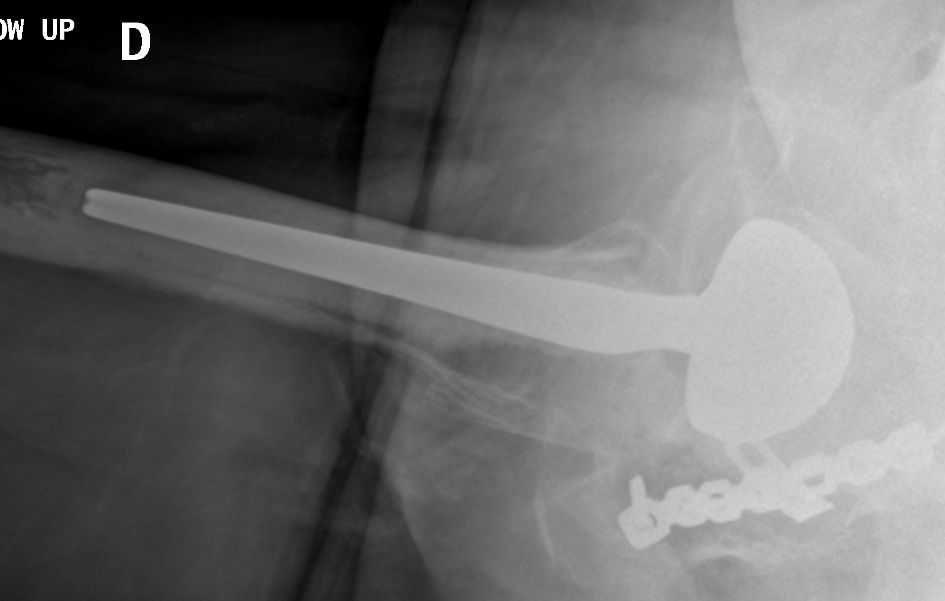

Using an LDH THA allows unrestricted movement after THA, for all types of surgical approaches. Vendittoli’s group in Canada does not impose any postoperative ROM restrictions for the posterior surgical approach, as it simplifies the patient education process, boosts their confidence during rehabilitation, and facilitates bilateral procedures[15,16]. LDH monobloc DM is especially interesting for many older women with large thighs and a small acetabular cavity (<50mm, Fig. 7).

In these cases, standard bearing diameters are prone to instability. With an LDH, a DM design provides optimal implant stability for these not-so uncommon patients. Moreover, with LDH we do not impose any activity restrictions in the long term. LDH CoC THA offers a major benefit for many active individuals since they can return to their regular jobs (e.g. plumber, roof worker, police officer, fireman) as well as for those who want to practice sports like rock climbing, kayaking, water skiing and martial arts.

Given the single neck diameter of most femoral stem designs, the head–neck ratio increases proportionally with the head diameter. Theoretically and clinically, this leads to a greater hip range of motion [18,19]. In addition, due to a supraphysiological arc of motion, extraarticular impingement is the first to occur whilst inter-component impingement is rare. Consequently, less-than-optimal implant positioning can be much better tolerated[20]. This is an important point considering the extent of surgical indications for patients with primary or secondary anatomical deformations (e.g. dysplasia, acetabular retroversion, previous pelvic osteotomy, post traumatic), because achieving an optimal implant position is often challenging (Fig. 7).

For the older, more sedentary and those with a shorter life expectancy, DM LDH THA is the ideal alternative (Figs 7 and 8).